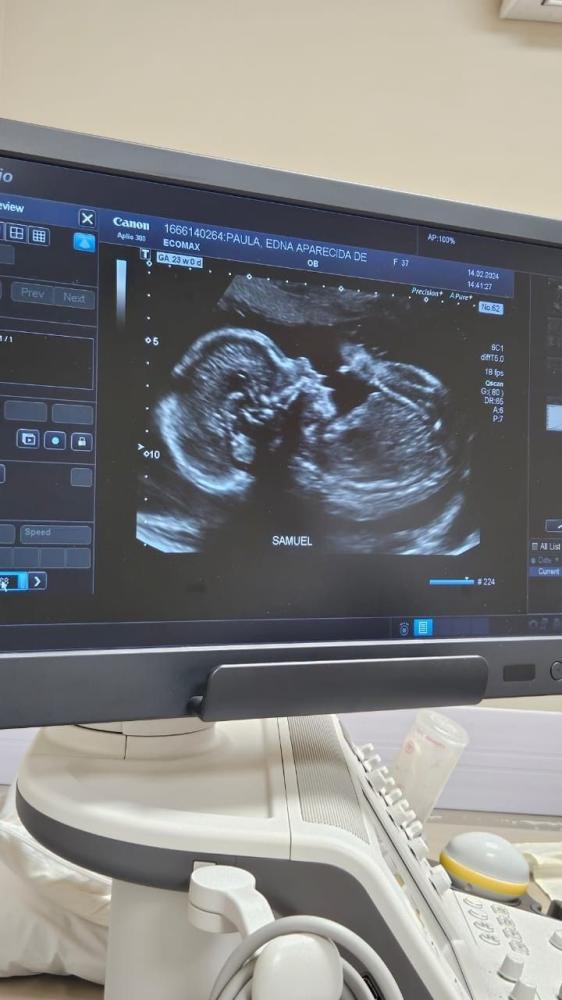

جلسة سونار الحمل مع التقرير توفر لك فحص شامل باستخدام جهاز سونار دقيق، مع شرح لحالة الجنين وتفاصيل نموه، بالإضافة إلى تقرير طبي مختوم يمكن استخدامه للمتابعة أو المراجعات.

الجلسة تُنفذ على يد أخصائية مؤهلة، وتركز على تقييم نبض الجنين، وضعيته، كمية السائل، والمشيمة، حسب عمر الحمل، وكل التفاصيل يتم تسجيلها بشكل واضح ومهني في التقرير.

• سونار للحمل (بطني أو مهبلي حسب المرحلة)

• تقييم نبض الجنين ووضعه ونموه